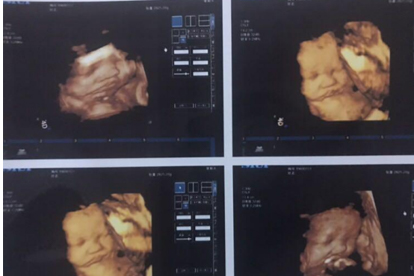

四维彩超怎么快速通过

四维彩超检查可以通过适量活动、提前沟通、选择时机、饮食准备、情绪放松等方式帮助快速顺利完成。